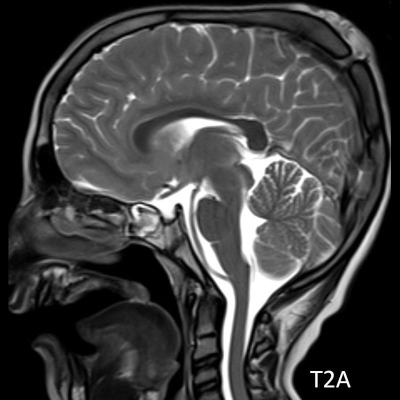

1. A) Kontrastlı FLAIR aksiyel görüntüde ve sagital T2A görüntüde vertekste orta hatta cilt altında dilate tortiyoze vasküler kollateraller (oklar). Paryetal kemikte orta hatta defekt (ok) ve defekt ile ilişkili vasküler yapıların cilt altı yumuşak dokulara uzanımı izlenmektedir.